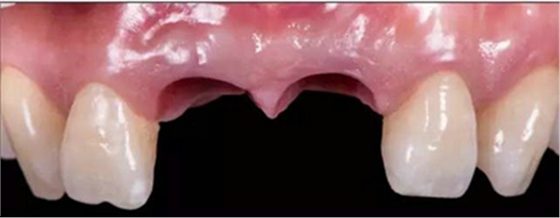

治療效果

修復(fù)前

修復(fù)后

本病例中通過(guò)對(duì)患者修復(fù)體佩戴后的舌側(cè)、頰側(cè)、左側(cè)、右側(cè)以及微笑照的采集,充分展示修復(fù)體在口內(nèi)的佩戴情況,可以看到無(wú)論顏色還是與鄰牙的匹配適宜度都是非常高,也比較吻合年輕女性對(duì)美觀的要求。同時(shí),通過(guò)術(shù)后多次隨訪及跟蹤患者后期使用狀況,患者也對(duì)修復(fù)效果十分滿意。